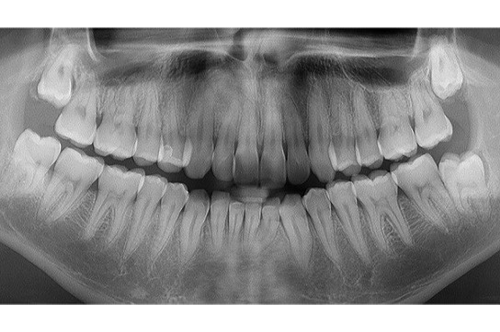

親知らずが生えてきたら、全て抜歯しなければならないか?と言えばそんな事はありません。レントゲン写真を見ると親知らずが4本全て真っ直ぐに生えています。このような場合は、親知らずを抜く必要がありません。以前は、日本の方でも多くの方が親知らずまで全て4本生えていましたが、現在は、顎の退化により親知らずが生えるスペースがないために、横や斜めに生えて悪さをするようになっております。